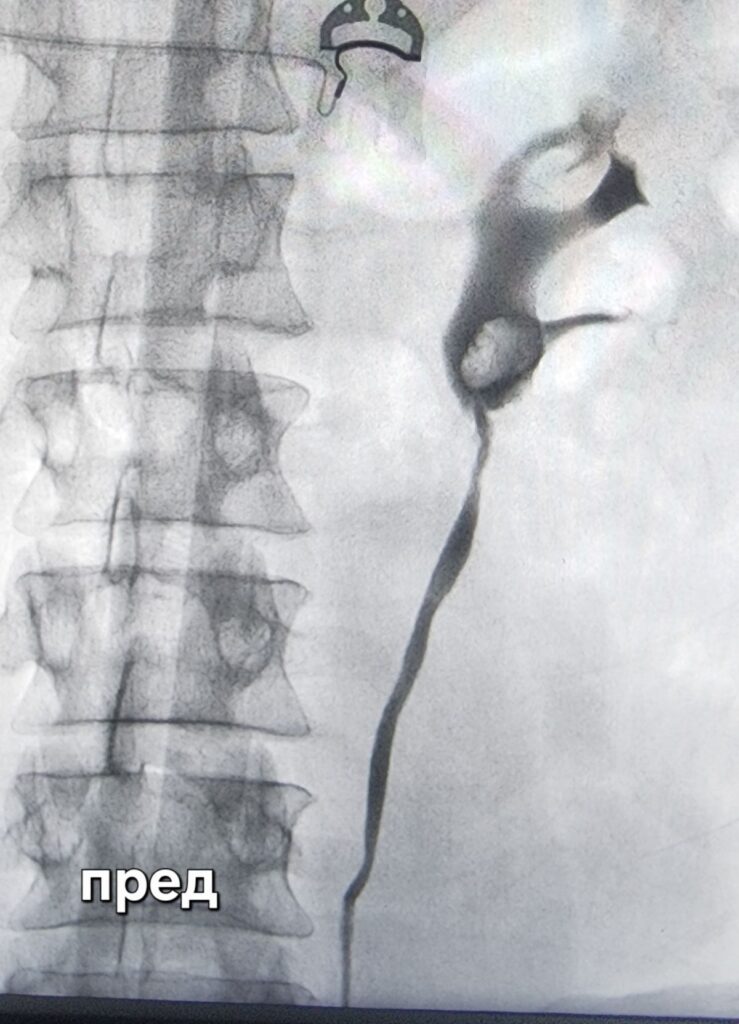

Во краткотрајна интравенска анестезија пациентот заспива и не чуствува ништо. Со цистоскоп се навлегува преку природните патишта. Откако ке се најдат отворите на уретерите (мочоводите од бубрегот до мочниот меур) се инстилира контраст во нив, при тоа со рентген се прават слики со цел да се визуелизира цел уретер. Со оваа снимка доста често можат да се видат и причинителите кои го затнуваат бубрегот.